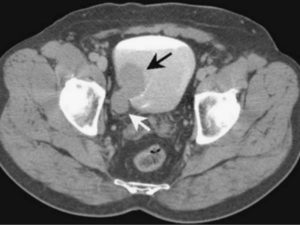

Часто проводится комплексное исследование КТ почек и мочевого пузыря, что показывает также аномалии развития мочевого пузыря, цистит, плоскоклеточный рак, аденокарциному мочевого пузыря, обструкцию шейки пузыря, метастатические поражения и другие патологии.

Основными признаками доброкачественных кист на КТ являются круглая форма образования с гладкой стенкой, четкими контурами, а также однородное содержимое плотностью менее 20 единиц.

После введения контрастного вещества плотность, форма и величина простой кисты не изменяется, при этом плотность паренхимы почки возрастает.

В нормальном состоянии мочевой пузырь также обычной формы, без деформации стенки, не определяются увеличенные или патологически измененные лимфоузлы, свободной жидкости не обнаруживается.